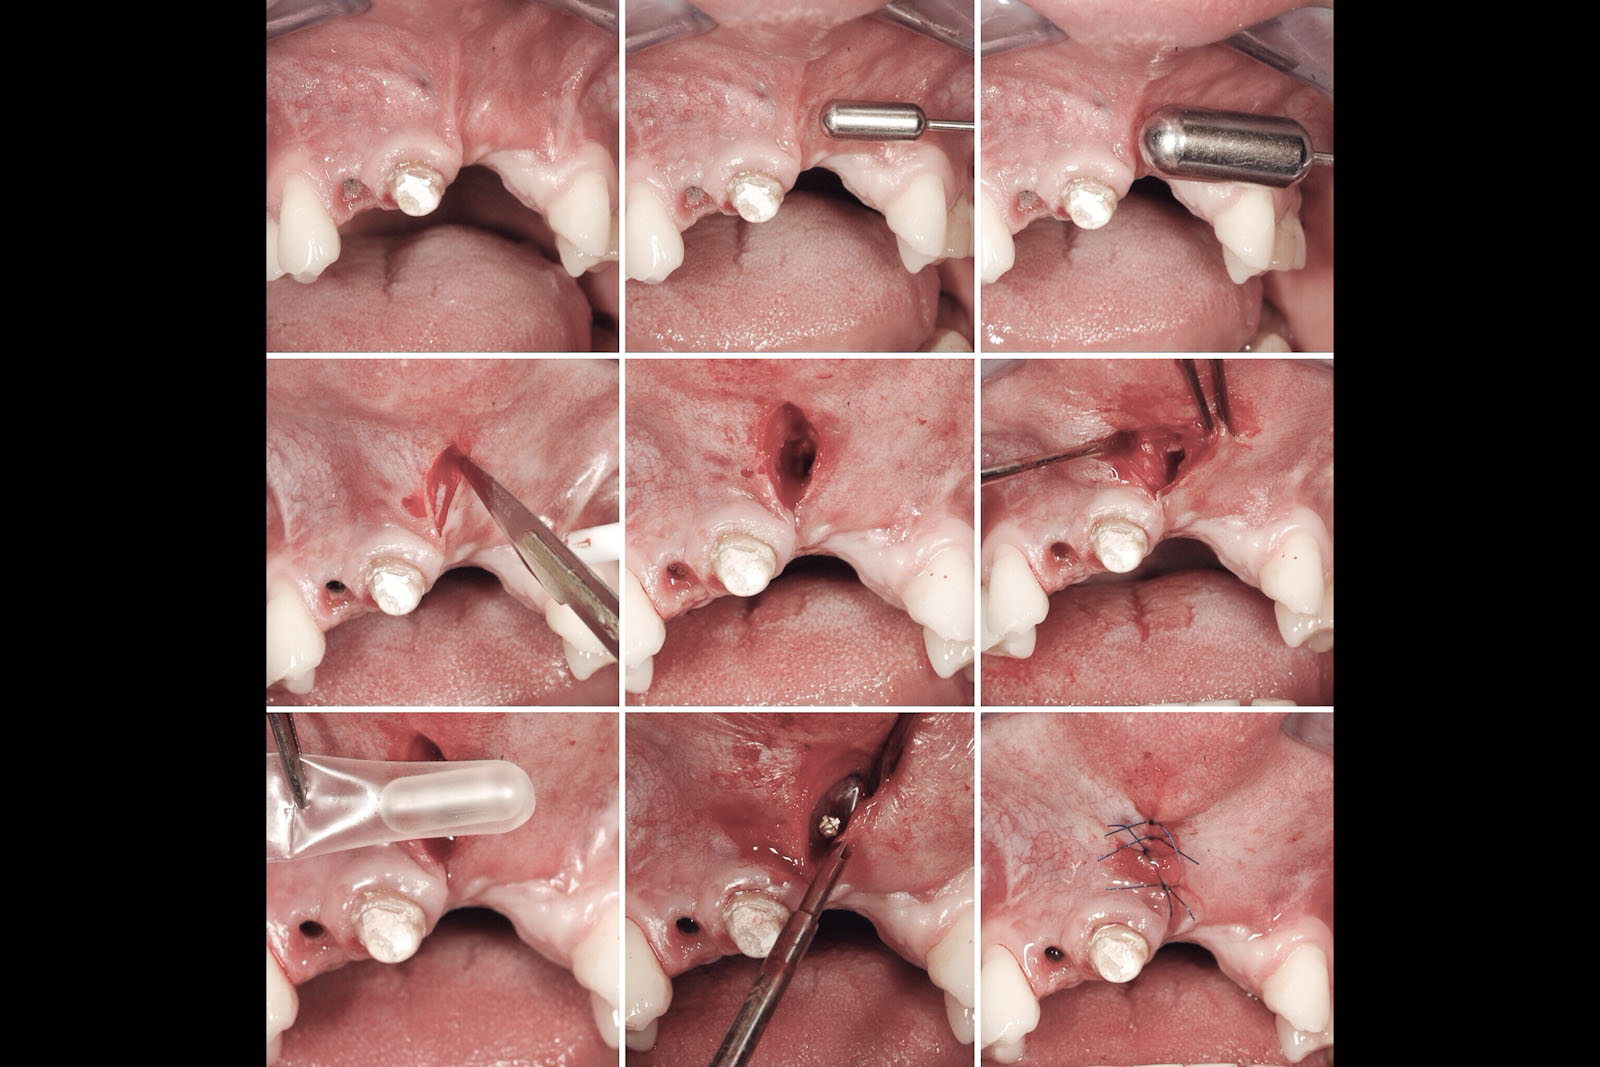

Zabieg odbudowy zębodołu powinno się wykonać możliwe jak najszybciej po usunięciu zęba. Jego celem jest odbudowa naturalnej objętości kości w miejscu utraconego zęba, a następnie szybkie wprowadzenie implantu. Najlepsze rezultaty uzyskuje się przy zastosowaniu biomateriału w formie bloczków kolagenowych lub granulatu, które dają trwałe efekty odbudowy oraz optymalną funkcję i estetykę odtworzonych koron zębów na wszczepionym implancie.

Procedury te są stosowane w sytuacji niedostatecznej ilości kości, skutkującej odsłonięciem gwintu, podczas gdy wszczepiamy implanty stomatologiczne lub też jako zabiegi poprzedzające ich wprowadzenie.​